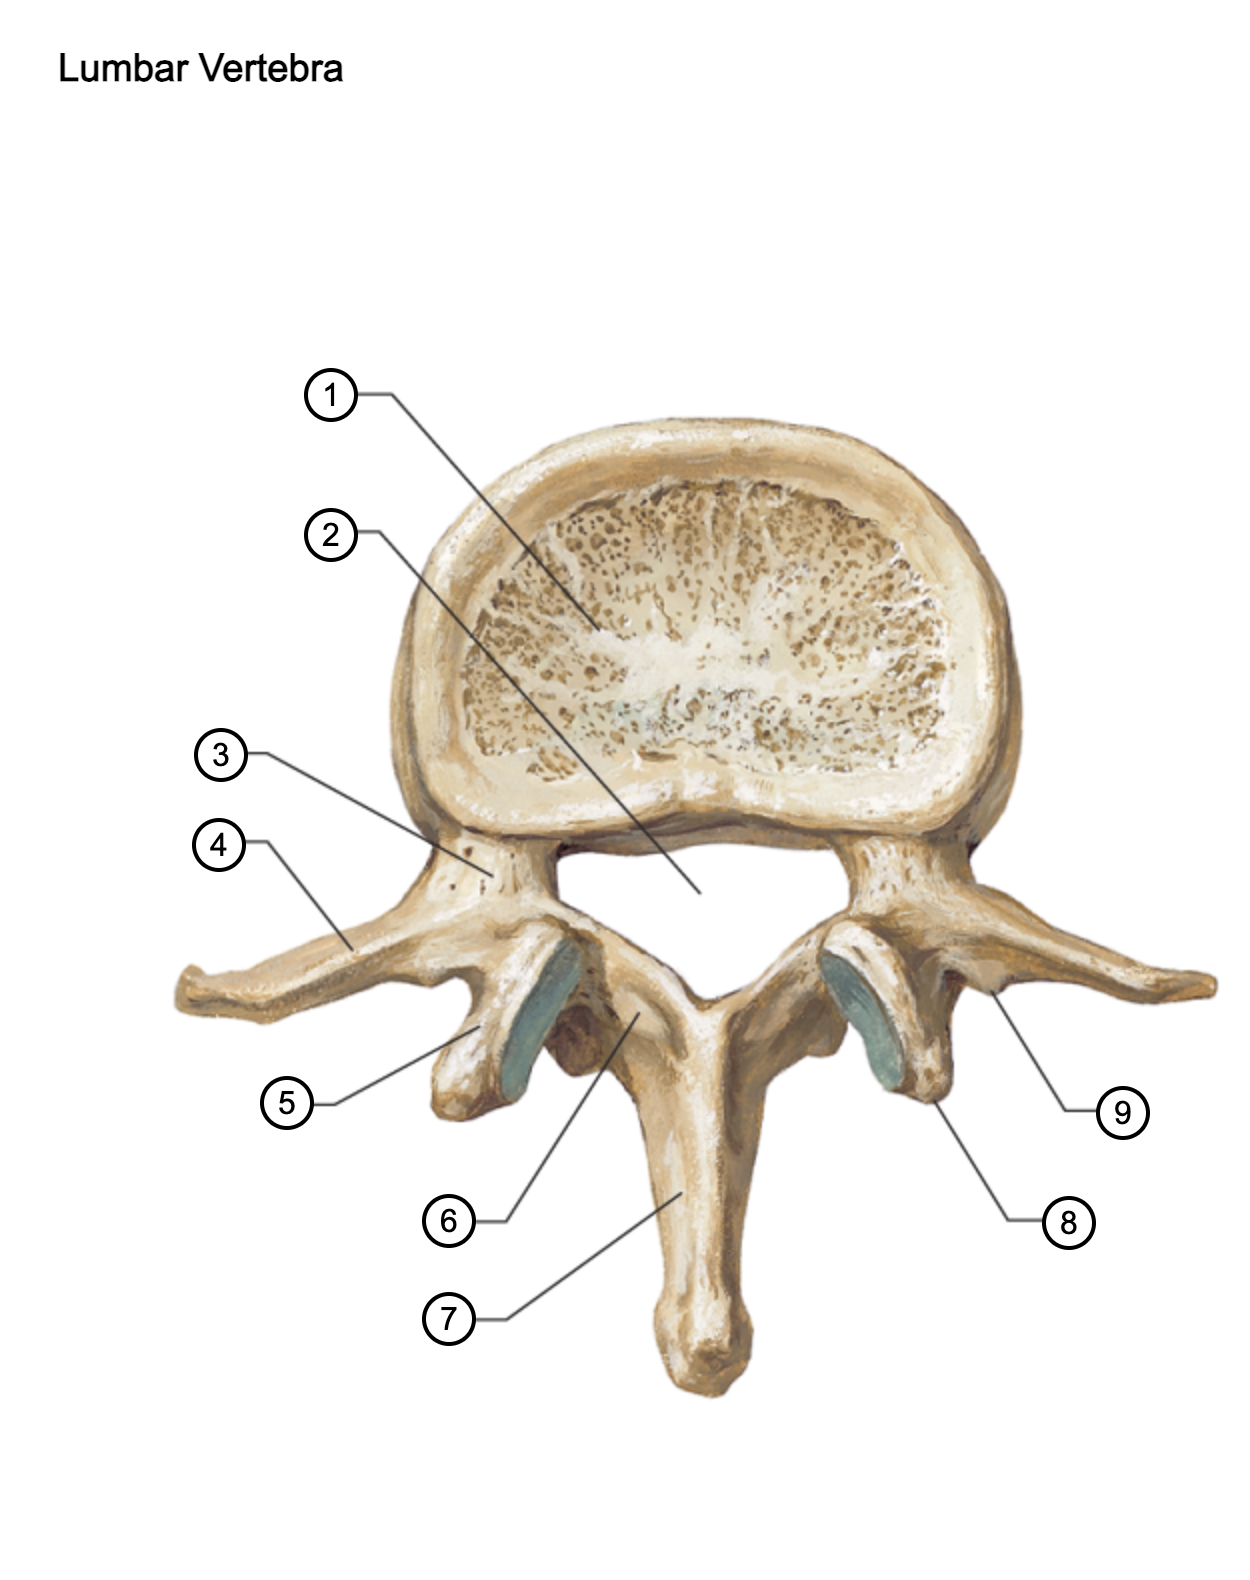

1

vertebral body

2

vertebral foramen

3

pedicle

4

transverse process

5

superior articular process

6

lamina

7

spinous process

8

mammillary process

9

accessory process